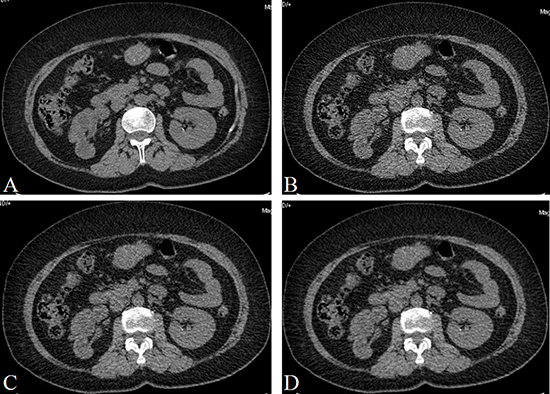

Some other diseases were found as followed: 52 patients had hydronephrosis as a subsequent disease, 10 patients had renal cysts (Figure 2), 7 patients had liver cyst, 6 patients had gallstone, and one patients had perinephric abscess. Inter-observer agreement between the two readers was substantial (κ-value = 0.65–0.73).

Figure 2: A 71 years old woman with several cyst in the renal. (A) CDCT images, reconstructed with FBP; (B) LDCT image, reconstructed with FBP; (C) LDCT image, reconstructed with 60% ASIR; (D) LDCT images, reconstructed with 80% ASIR. The image quality was poor in B, and the image quality were similar in A and D.

The CDCT images were reconstructed with FBP and the LDCT images were reconstructed with FBP, 40% ASIR, 60% ASIR and 80% ASIR, repectively. The scores of image quality, image noise and diagnostic confidence were showed in Table 2. The LDCT images reconstructed with FBP had a poor image quality (mean score, 2.77), which was lower than the CDCT images reconstructed with FBP (mean score, 4.17) and the LDCT images reconstructed with 80% ASIR (mean score, 4.09). There were no significant difference between the CDCT images reconstructed with FBP and the LDCT images reconstructed with 80% ASIR with regard to the image quality (P = 0.229) (Figure 3).

Figure 3: A 50 years old man with a small stone (1.8 mm × 1.6 mm × 1.7 mm) in the left renal. (A) CDCT images, reconstructed with FBP; (B) LDCT image, reconstructed with FBP; (C) LDCT image, reconstructed with 60% ASIR; (D) LDCT images, reconstructed with 80% ASIR. The image quality was poor in B, and the image quality were similar in A and D.